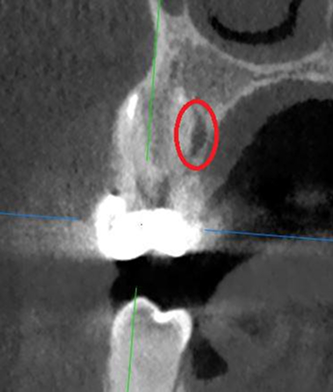

Лечение: Проведено перелечивание корневых каналов под микроскопом с удалением ранее внесённых материалов, тщательной механической и медикаментозной обработкой каналов и их последующей герметичной обтурацией. После лечения каналов выполнено восстановление коронковой части зуба.